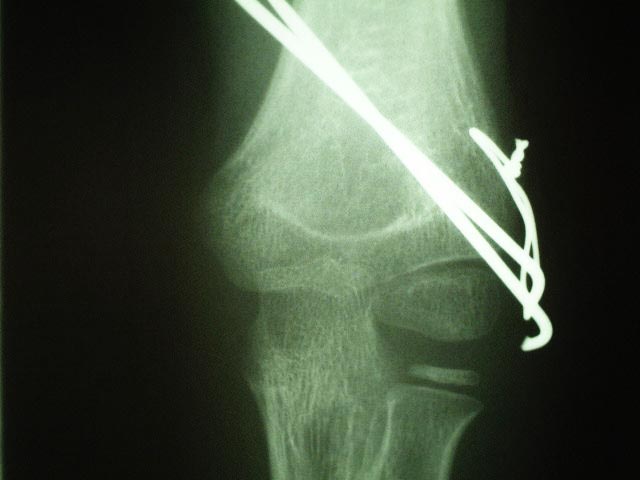

2)手術的治療

徒手整復術で良好に整復されても、すぐ転位するような不安定な症例は

経皮的骨接合術(切開せずに皮膚の上からピンのような器具で骨折部を固定する手術)を行います。また、徒手整復が困難な症例(骨片が回転している症例転位のある症例)は骨接合術を検討します。上腕骨外顆骨折は正確に整復されないと、偽関節(骨折が完全に付かない状態)や外反変形などの後遺症を残し、将来、変形性肘関節症となりますので正確な診断と整復固定が必要です。